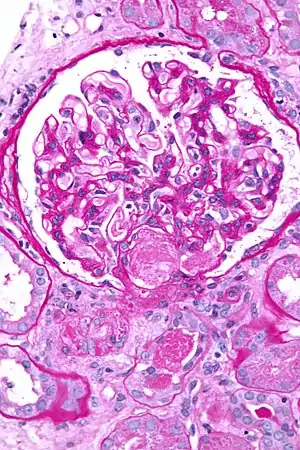

Micrograph showing acute thrombotic microangiopathy due to DIC in a kidney biopsy. A clot is present in the hilum of the glomerulus (center of image).